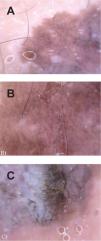

Presentamos el caso de una mujer de 48 años, sin antecedentes personales ni familiares de interés, que fue remitida a la Unidad de Melanomas de nuestro Servicio con el diagnóstico de sospecha de «melanoma en región perianal». La paciente refería que la lesión apareció aproximadamente tres años antes y que había crecido lentamente desde entonces. A la exploración, en la región perianal observamos un tumor pigmentado de 3,5 × 2 cm de diámetro, asimétrico en ambos ejes, de bordes mal delimitados, policromo y de superficie blanquecina escamosa (fig. 1). Con dermoscopia (fig. 2) (sistema FotoFinder) no apreciamos la presencia de retículo pigmentado, estrías radiales, ni otros hallazgos dermoscópicos característicos de lesiones melanocíticas, a excepción de un agregado de glóbulos de morfología y tamaño irregular en uno de los segmentos del tumor. En el resto de la lesión predominaba un patrón vascular atípico, compuesto por estructuras de gran tamaño, tortuosas, irregulares, siendo alguna de ellas de morfología redondeada. En la porción inferior de la lesión se apreciaba una zona verrugosa de superficie blanquecina. La biopsia mostraba un tumor confinado a la epidermis con acantosis, cierta papilomatosis, atipias celulares marcadas y figuras de mitosis, estando completamente conservada la membrana basal. Se emplearon técnicas inmunohistoquímicas como el Melan-A y el cocktail de pancitoqueratinas, que confirmaron la naturaleza del tumor, estableciendo el diagnóstico de EB pigmentada. Realizamos la extirpación quirúrgica de la lesión y tras dieciocho meses de la intervención la paciente continúa asintomática.

La dermoscopia es una técnica no invasiva que mejora la precisión diagnóstica de las lesiones pigmentadas. Se han descrito varios patrones2,3,8-10 dermoscópicos de la EB, en los que quedan recogidos los hallazgos más característicos y frecuentes de este tumor (tabla 1). Elpatrón dermoscópico que aparece con mayor frecuencia en la EB es el patrón multicomponente8. De todos los parámetros recogidos en la tabla 1, los más específicos de la EB son la presencia de un patrón vascular atípico (86,6-90%) y de una superficie tumoral escamosa o verrugosa (64,2-90 %)3,8. Dicho patrón vascular puede estar compuesto por vasos de morfología irregular, tortuosos, arboriformes, puntiformes, etc. Para algunos autores3,9,10 estas estructuras vasculares son específicas de la EB y las denominan «vasos glomerulares»10, por su morfología especial y su semejanza con los vasos del glomérulo renal. Refieren que se trata de estructuras vasculares similares a los vasos puntiformes que pueden aparecer en el melanoma amelanótico, pero de mayor tamaño y morfología en espiral. Las formas pigmentadas de EB, además de los criterios anteriormente mencionados, se caracterizan por la presencia de glóbulos (90 %) y áreas de pigmentación gris marrón homogénea (80 %)3. Estos glóbulos suelen ser de menor tamaño que los que aparecen en las lesiones melanocíticas y característicamente se distribuyen de forma parcheada en algunos segmentos de la lesión. En el caso que presentamos encontramos tres de los cuatro criterios dermoscópicos de la

EB pigmentada (patrón vascular atípico, superficie escamosa o verrugosa y glóbulos de distribución parcheada). Sin embargo, no podemos afirmar la presencia de los específicos «vasos glomerulares», sino más bien un patrón vascular atípico. A pesar del gran valor de los parámetros dermoscópicos descritos para la EB, es necesario destacar que todos ellos pueden aparecer también en tumores melanocíticos benignos, queratosis seborreicas, carcinomas basocelulares y en el melanoma. Por ello, creemos que no son del todo fiables para realizar un correcto diagnóstico diferencial con el resto de las lesiones pigmentadas, especialmente con el melanoma, siendo la anatomía patológica el patrón oro para diferenciarlos con exactitud. El caso que presentamos refleja la complejidad del diagnóstico de la patología tumoral cutánea, sobre todo cuando se presenta con características clínicas y dermoscópicas comunes a varios tumores, en una edad diferente a la habitual y con localización atípica.